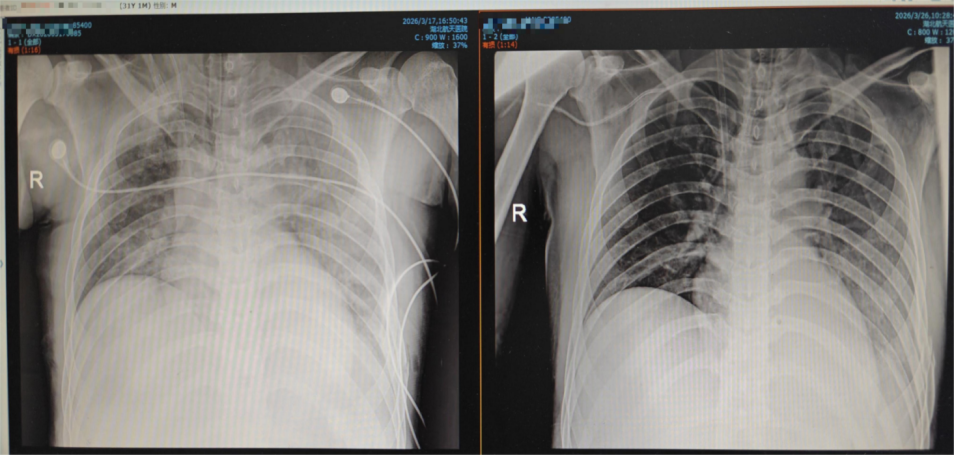

胸部DR对比:ECMO上机前和撒机前

经过16天的精准救治与悉心守护,患者病情持续好转:3月26日,ECMO撤机试验成功,患者氧合指数可维持在300mmHg以上,达到正常水平;3月27日,纤支镜引导下经皮气管切开手术顺利完成,出血量不足2ml;3月30日,患者神志完全转清,肢体活动正常,可遵嘱完成简单动作;3月31日,患者成功脱离呼吸机,生命体征平稳,这场长达16天的生死救援圆满取得胜利。